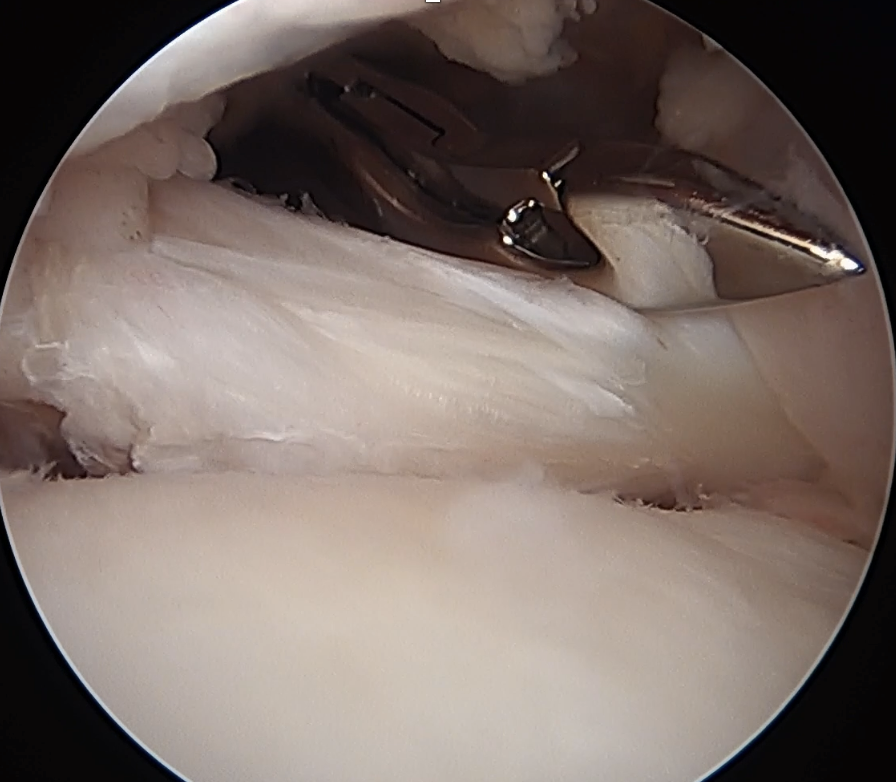

Medially dislocated biceps tendon with upper border subscapularis tear

Full thickness tear of subscapularis off insertion revealed with grasper